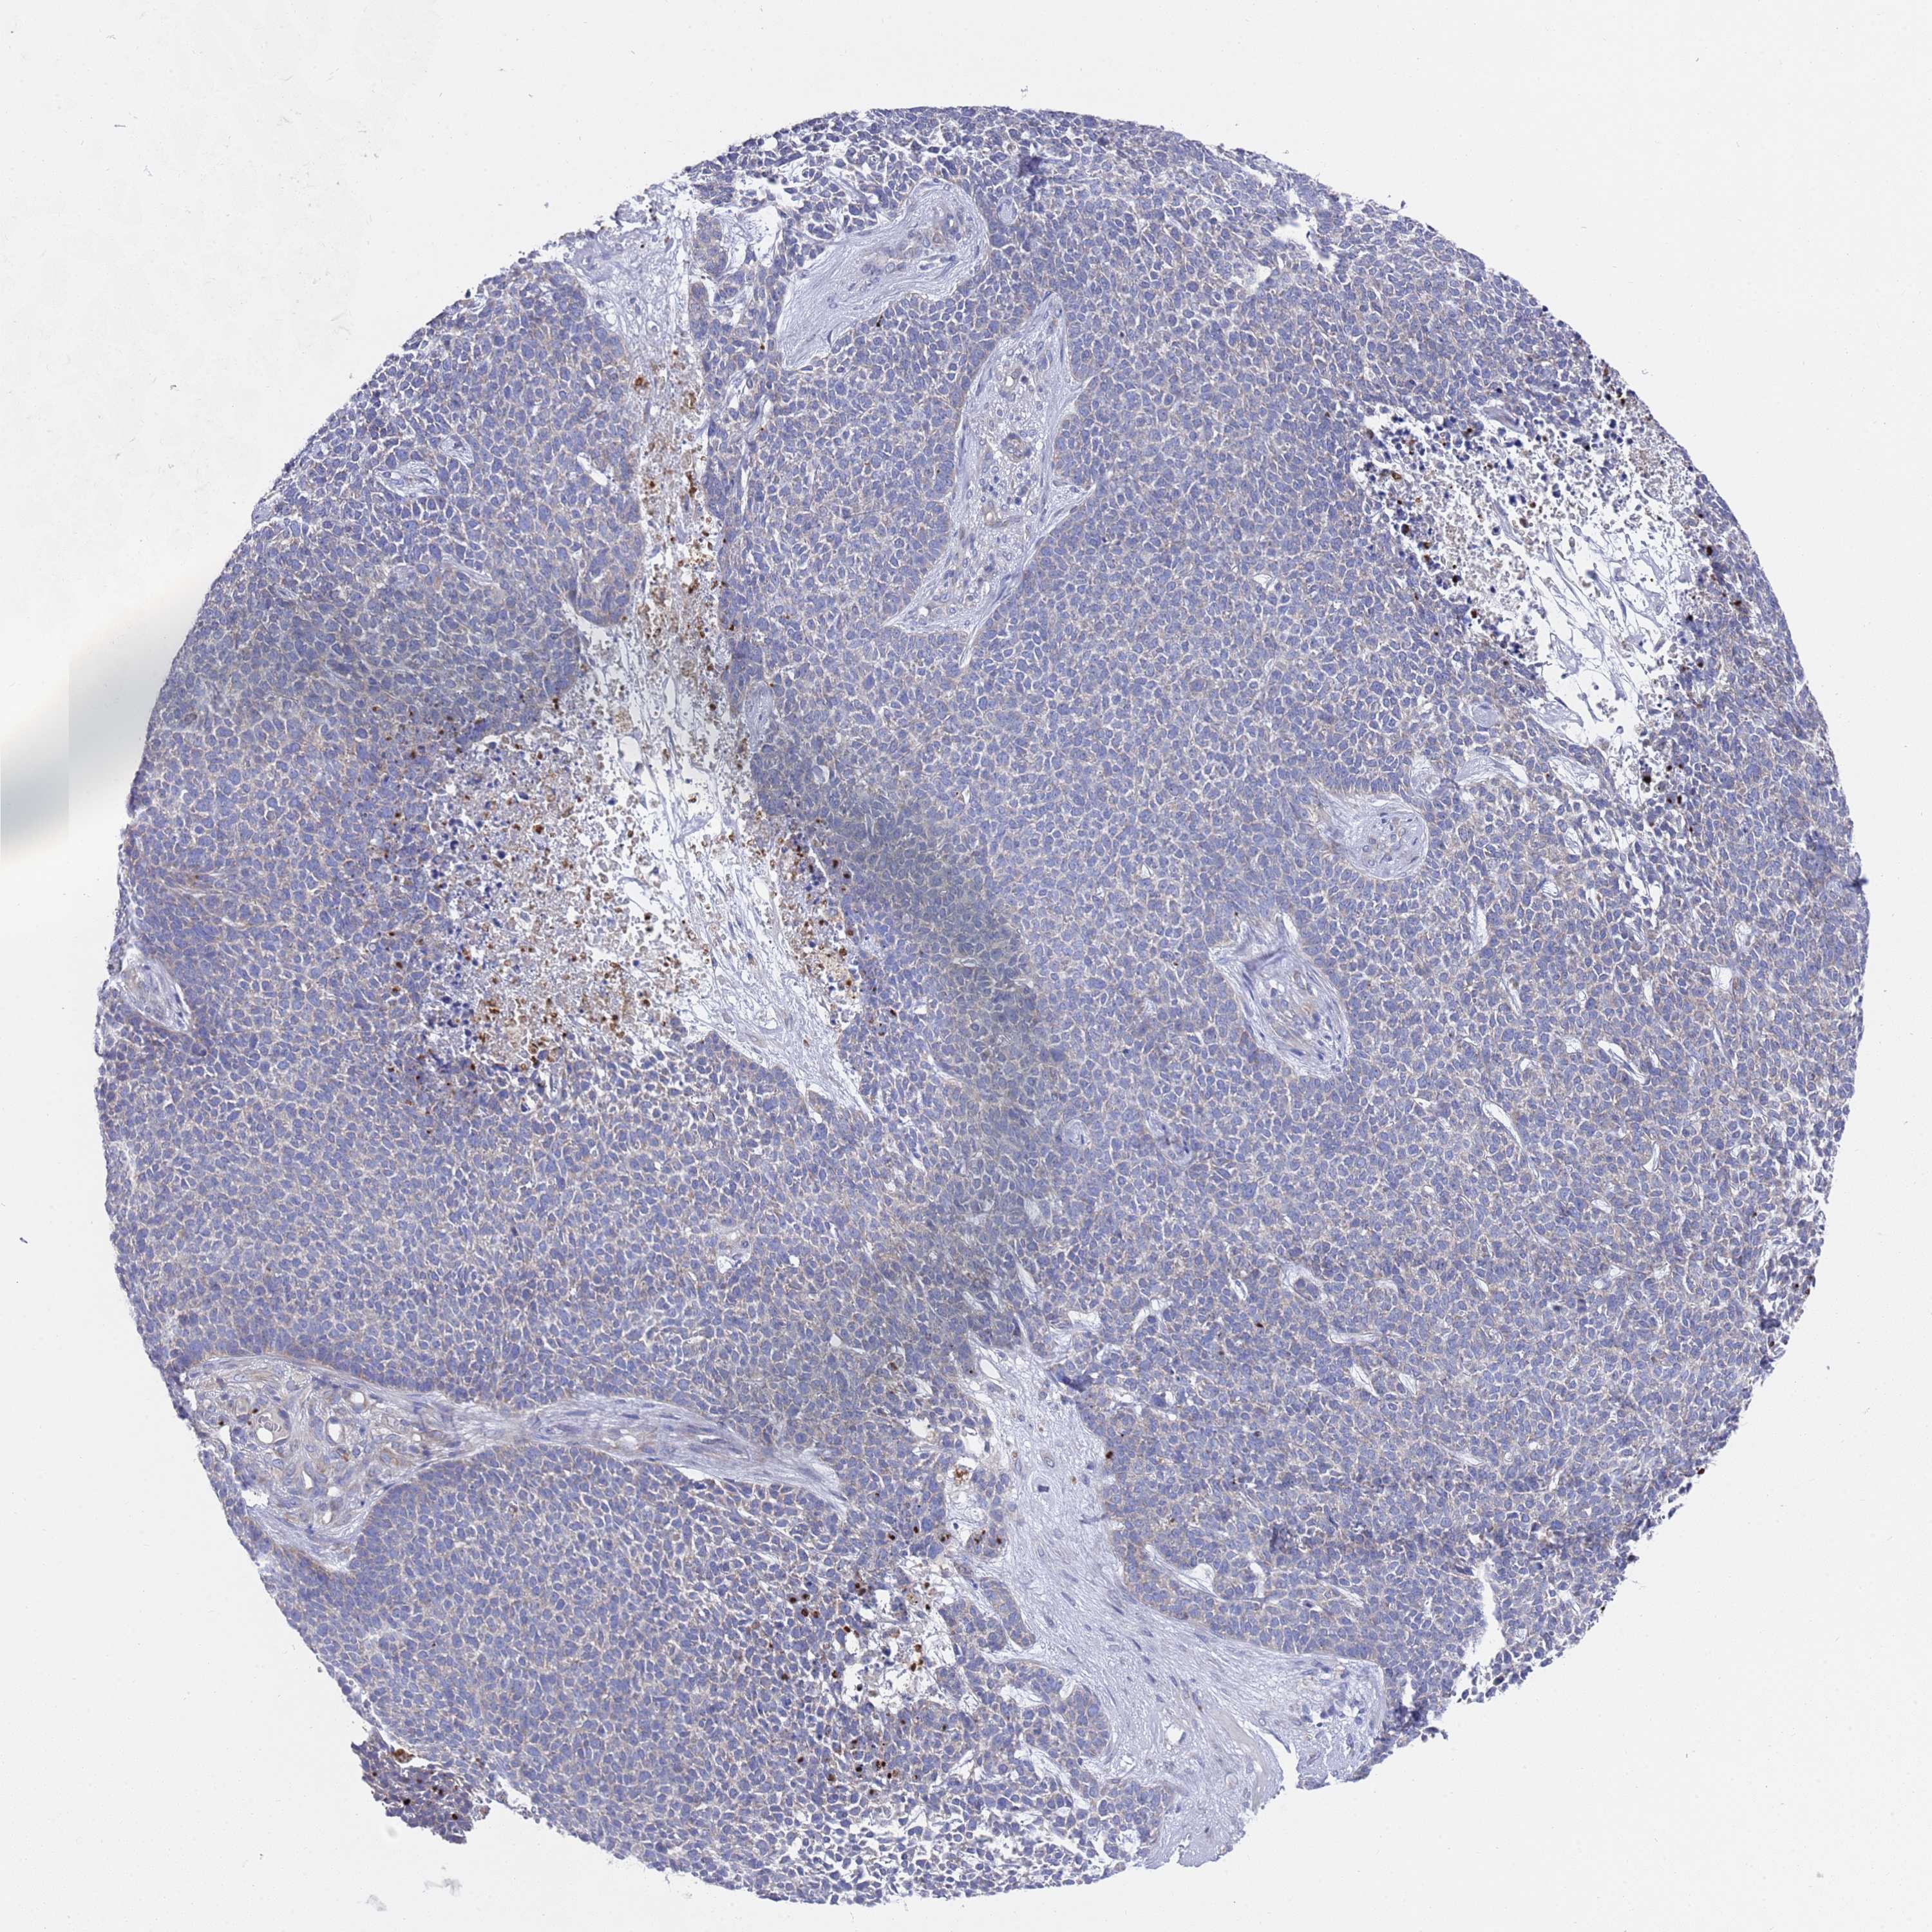

SKIN CANCER - Protein expressioni

A mouse-over function shows sample information and annotation data. Click on an image to view it in a full screen mode. Samples can be filtered based on level of antibody staining by selecting one or several of the following categories: high, medium, low and not detected. The assay and annotation is described here.

Each image is clickable and will lead to virtual microscopy that enables deeper exploration of all samples and also displays staining intensity scores, fraction scores and subcellular localization as well as patient and tissue information for each sample.

Antibody HPA045649

Squamous cell carcinoma, metastatic, NOS